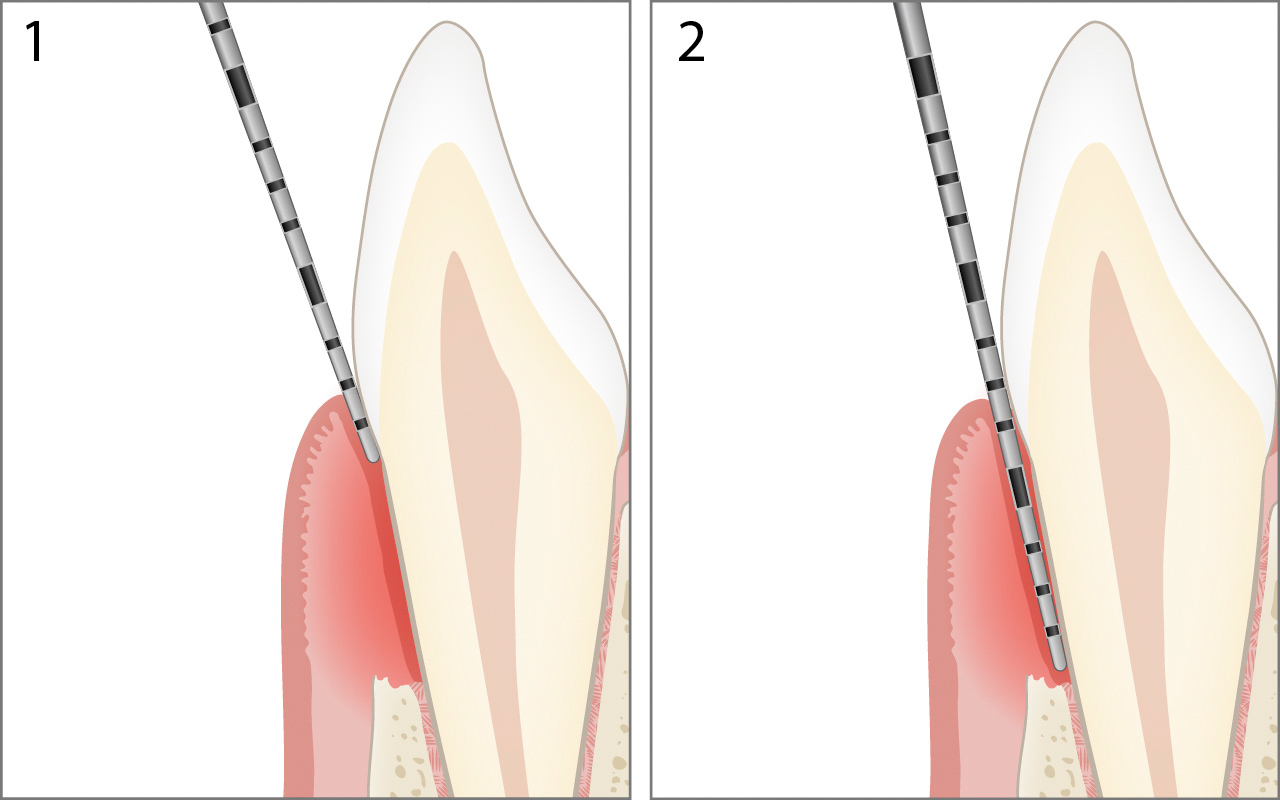

Parodontale Tasche

Im erkrankten Parodont kann die Schmelz-Zement-Grenze über oder unterhalb des Gingivalrandes liegen. Die Distanz vom Gingivalrand zum Boden der parodontalen Tasche wird als Sondierungstiefe 2 festgehalten.

Die Berechnung des Attachmentniveaus in der oben gezeigten Abbildung lautet:

Attachmentniveau 5mm = Sondierungstiefe 7mm – Margo Gingivae 2mm

Beachte: Taschen ab 4mm, die nach durchgeführter Parodontaltherapie noch vorhanden sind, werden als Resttaschen bezeichnet.